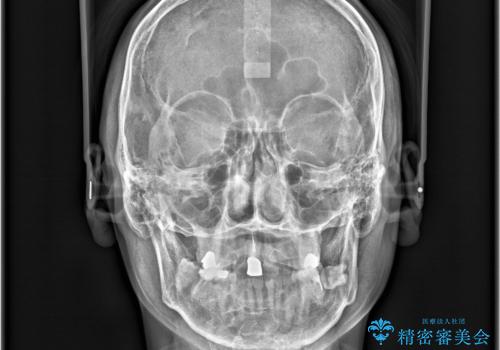

- 「八重歯と歯のでこぼこを治したい」を主訴に来院された患者様です。

歯は抜かずに奥歯の遠心移動とIPRで八重歯とでこぼこを改善しました。

左上3番は保険治療(CR)の劣化による二次カリエスになっていますので、後日治療予定です。